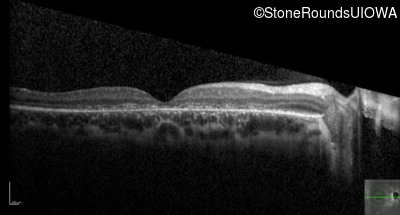

Optical Coherence Tomography - Left - 20/200 -2

Exemplar / OCT Stack